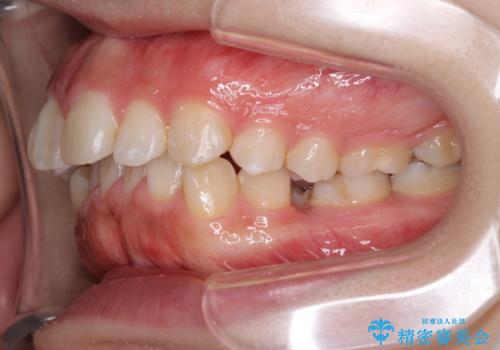

がたがたと出っ歯を直したい ワイヤーによる抜歯矯正

- ガタガタと出っ歯を主訴に来院されました。

上下左右の歯を1本ずつ、合計4本抜歯してワイヤーにて矯正治療をすることとなりました。

前から4番目の歯を抜歯することが多いのですが、右上の前から5番目の歯が神経の治療済みであり、こちらの歯を抜歯する計画としました。